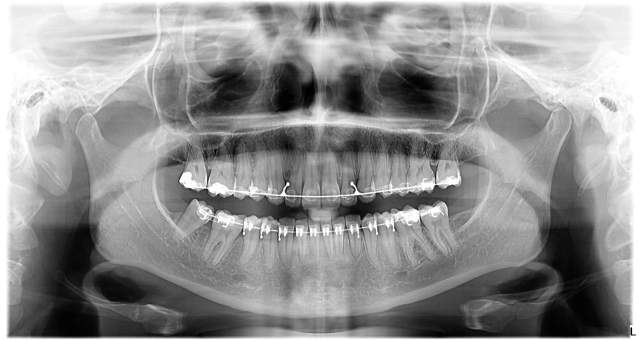

Braces are one of the most common methods of orthodontic treatment. These small tools made of metal or ceramic materials are glued to your teeth and joined with a special wire. By stretching this wire, the teeth slowly move towards the desired position. Hospitapirme Dental Clinic offers both traditional metal braces and more aesthetic ceramic braces.